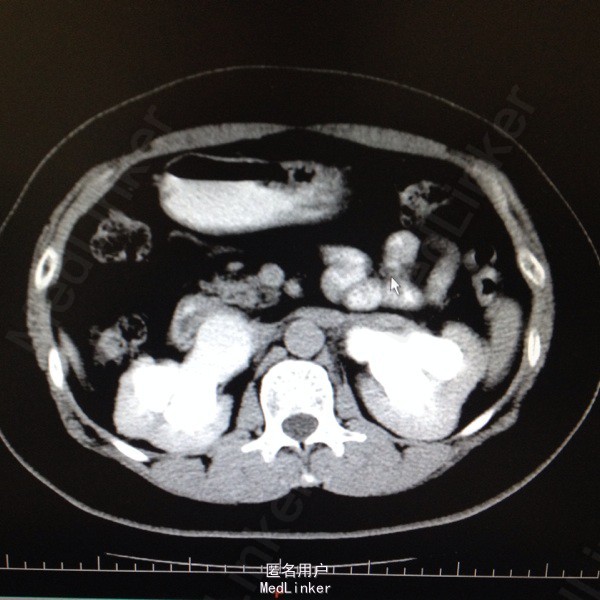

47岁女患。 病史:患者6年前因宫颈癌行全子宫及双侧附件切除。盆腔淋巴结清扫。腹主动脉旁淋巴结活检术。后又行局部放疗。因双肾积水来我科。患者自述平时轻微排尿困难,尿线细。

双肾区无叩击痛,双输尿管走形区无压痛。耻骨上区隆起,叩诊浊音。排尿后留置尿管引流尿液400ml。 辅助检查:肌酐99。 ct:双肾及输尿管积水。 留置尿管后一周泌尿系彩超:双肾积水明显减轻。具体见图片。

诊断:双肾及双输尿管积水 神经源性膀胱 给予患者留置尿管后1周行泌尿系彩超检查肾积水减轻。